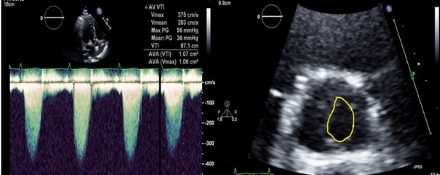

Case: A 29-year-old female with history of congenital bicuspid aortic valve, G1P0 presented at 42+2 weeks of pregnancy and was admitted to cardiac intensive care unit for continuous hemodynamic monitoring via use of arterial line. Her prior aortic valve disease was treated by valve repair with valvotomy, removal of tissue from pseudo raphe, removal of calcified scar tissue from both commissures, and a mitral valve repair for closure of an iatrogenic tear in her anterior leaflet. She followed closely with maternal fetal medicine and cardiology but became symptomatic at week 28 with lightheadedness, shortness of breath and decreased exercise tolerance (NYHA Class II). By week 33 she noticed lower extremity edema. Despite recommendations for planned delivery, she opted to wait until full term for delivery. Surveillance echoes revealed rising velocities yet stable valve area by planimetry. She ultimately underwent an uncomplicated Cesarean delivery of baby boy in week 42. At 6 months post partum she had successful transcatheter aortic valve replacement.

Discussion: As the severity of valvular disease worsens there is a higher risk of complications during pregnancy. In our case, aortic valve velocities were elevated due to the expected hemodynamic changes of pregnancy. Thus, echocardiography monitoring should be used to assess the left ventricle’s ability to tolerate and compensate for these changes, while intervening based on symptoms and NYHA classification. We highlight the importance of multidisciplinary collaboration for safe and successful delivery in patients with AS.